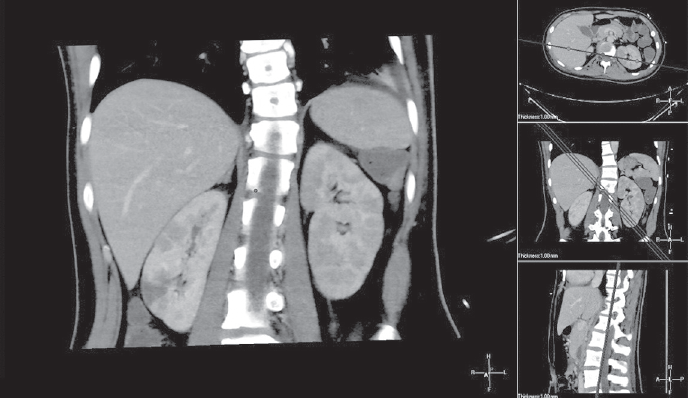

The optimal time for surgery on the heart valves in patients with active infectious endocarditis (IE) is still controversial. It is a well known fact that cerebral, coronary or renal thromboembolism is the most common cause of death in patients with left-sided IE. Thromboembolism can develop before the appearance of clinical manifestations of the destruction of the valvular apparatus of the heart. Currently, early surgical intervention is considered as the most effective method of treatment of many forms of active left-sided IE. Early surgery involves performing surgical correction until the completion of a full antibiotics course. We present the clinical case of early surgical correction of the patient (A., 16 years) with mitral valve infectious endocarditis. The disease was acute, with recurrent embolisms to the right kidney with infarction and to the left clavicle with osteomyelitis. Surgical intervention was performed as a matter of urgency; surgical access – right-sided anterolateral thoracotomy. The girl was operated on the 4th day of the hospitalization to our hospital. However, time of treatment was lost at the prehospital stage and rapid mitral valve destruction did not allow to repair the valve. Therefore, the mitral valve replacement was performed. The postoperative period was favorable. On the 3rd day after the operation, the girl was transferred to the cardiology department. On control ECHO after 3 years: myocardial contractile function is good, EF 65%, the function of the MV prosthesis is not impaired.